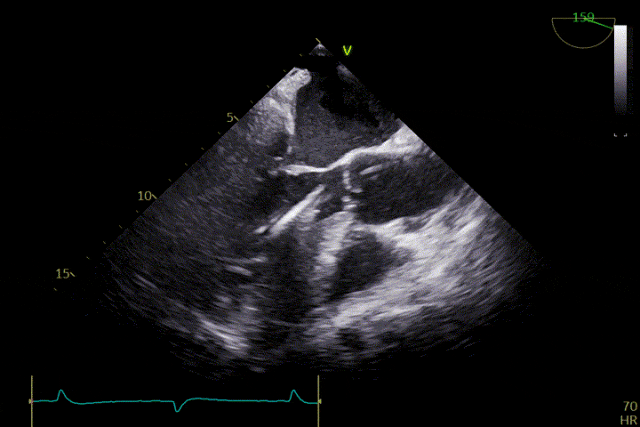

术前超声

患者主动脉瓣重度反流纠正,术后无反流、无瓣周漏。术后心脏彩超显示人工生物瓣启闭良好,平均跨瓣压差2mmHg,流速正常。患者恢复情况良好,心功能较术前有了明显改善。